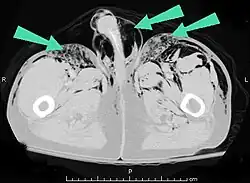

Additionally, it may result from self-injection of air during illicit drug use, particularly in individuals who inject substances intravenously or into unusual sites. There have been documented cases of subcutaneous emphysema occurring in various body regions, including the scrotum, secondary to such self-induced air injection during substance abuse.[23]